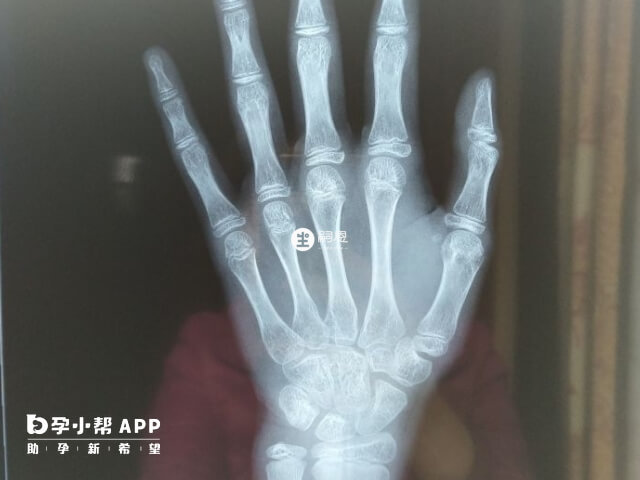

骨龄是骨骼年龄的简称,骨龄和年龄不一定一致,它代表的是骨成熟度,反映的是生物年龄。骨龄需要借助于骨骼在X射线摄像中的特定图像来确定,通常要拍摄人左手手腕部的X射线片,医生通过X射线片观察左手掌指骨、腕骨及桡尺骨下端骨化中心的发育程度进行评估。下面是10-16岁儿童的骨龄身高表,大家可以参考: